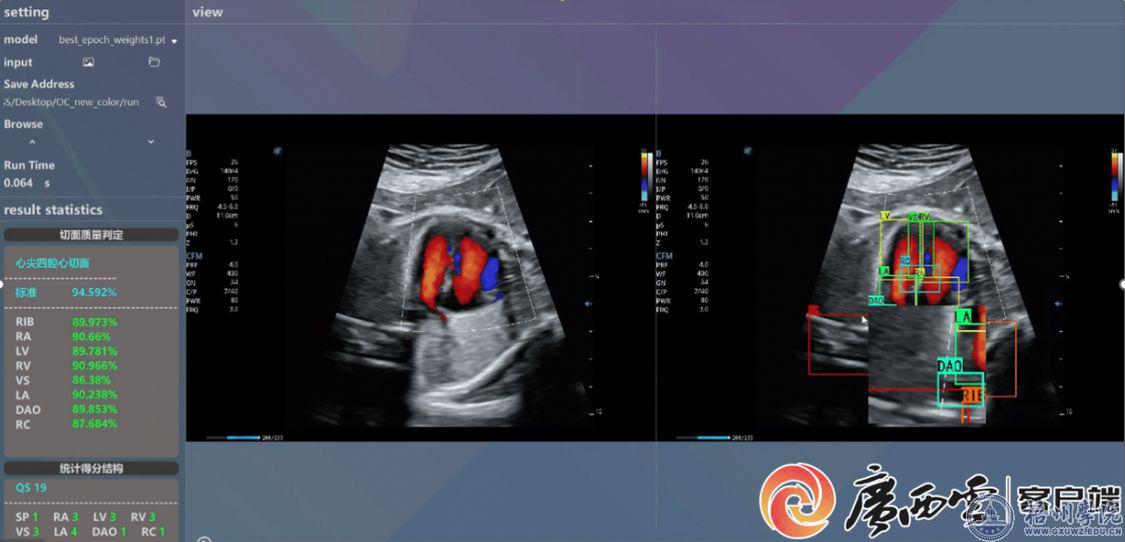

梧州学院数智媒体技术团队开展了医学信息处理方面的人工智能研究。与深圳妇幼保健院、梧州市人民医院开展多模态医学数据的人工智能处理,主要是针对优生遗传相关的影像、病理及子代随访数据进行分析,包括胎儿发育预测、出生缺陷辅助诊断、女性子宫多种病变的辅助诊断。已拥有近3万胎儿超声影像数据、超1万例0至6岁新生儿子代随访数据、超3万张子宫内膜癌影像数据集及10余万张显微影像。有关目标域数据增强、孕妇睡眠周期调节、胎儿先心病超声质量控制、显微视频传输的成果在Information Fusion、IEEE Transactions on Broadcasting、Future Generation Computer Systems、Neurocomputing等顶级期刊发表。与梧州市人民医院已于2023年共建了医学影像人工智能联合研究中心,于2024年1月在梧州市医学会放射学分会年会开展有关医学影像AI应用的学术讲座,并联合承担了2025年广西自然科学基金项目“面向子宫内膜癌多模态图像智能辅助诊断的关键技术研究”,利用人工智能技术对子宫内膜癌的数字病理切片及MRI切片影像进行良恶性分类及全局病变程度分析。

开发的胎心超声标准切面质量控制软件。